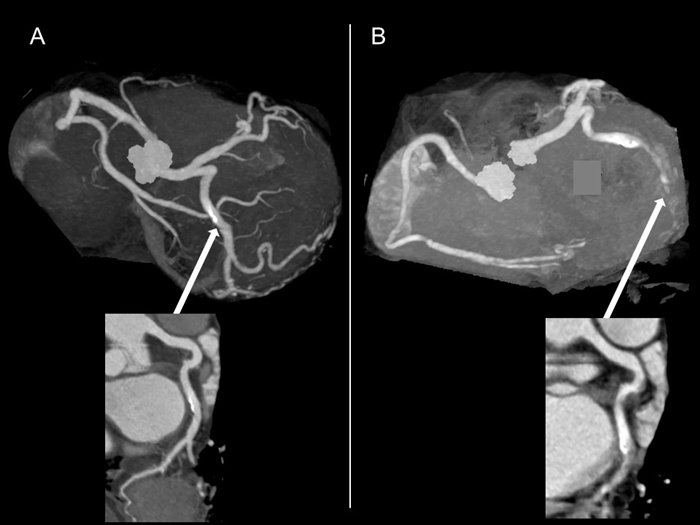

高心拍数による画質低下

A: HR <65/min で撮影. B: HR >90 /minで撮影.

上の画像ではAが撮影時の理想的な心拍数 65/分以下で撮影した画像で、Bが心拍数 90/分以上で

撮影した画像で、同じ人の別な時期に撮影した画像ですが, 矢印で示した回旋枝の画像が、Bでは

狭窄度の診断が困難なほど画質が低下しています。

冠動脈CTの診断能確保のためには、理想的な心拍数を確保するため、内服または注射のβ遮断薬を

使用します。